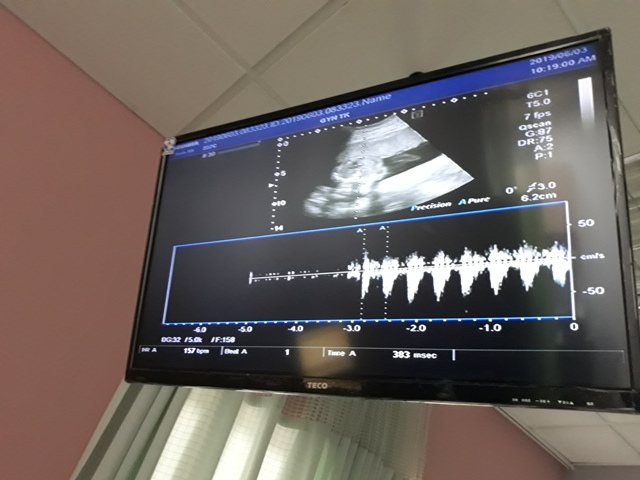

早上十點左右,和小純至澄清醫院做產檢,今日要做的是『妊娠糖尿病』的檢查(一般來說,妊娠糖尿病是24週 - 28週檢查,不過小純今天是第23週又3天,還沒到24週),首先我們先到抽血室去,護理師拿了五瓶裝的美達妍注射液讓小純喝,喝完之後一個小時以後再進行抽血。來之前小純有跟我說過,驗妊娠糖尿病要喝很甜的 糖水,但她今天喝了,感覺還好,不會很甜。

| 2019年06月03日 | 58.3mm(9%) | 179.6mm(12%) | 38.2mm(10%) | 584g(43%) | 157 |

| BPD:胎兒頭骨橫徑 AC:胎兒腹圍的長度 FL:胎兒大腿骨的長度 EFW:胎兒的體重 括弧內百分比為較上次產檢的成長比例 | |||||